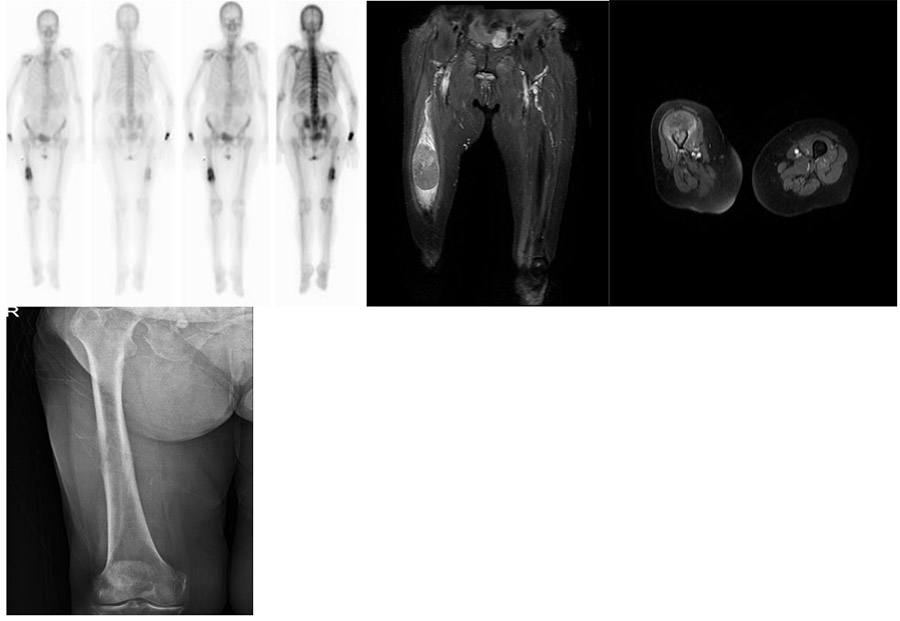

Before the surgery: X-ray shows bone destruction in the midline of the right femur, MRI shows an accompanying soft tissue component, and scintigraphy shows a single metastatic focus.